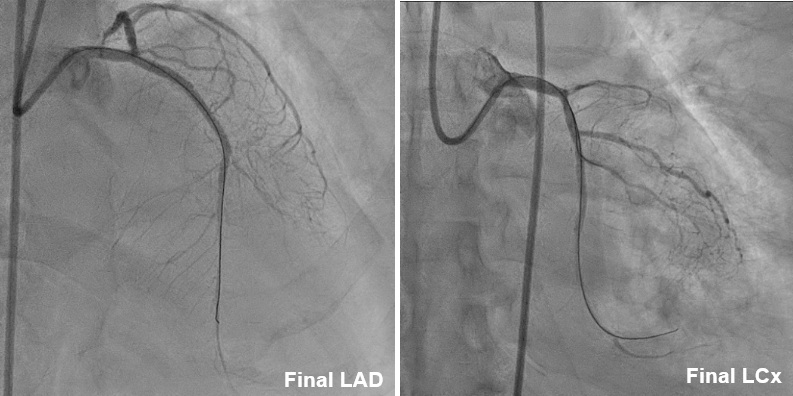

After finishing PTCA of LCx, we then coped with LAD CTO. We passed the 1st CTO lesion of LAD with XT-A , successfully advanced to the diagonal branch. However, 2nd CTO lesion was noted over bifurcation of 2nd diagonal branch and LAD. We then advanced SASUKE double lumen catheter with UB3 for better controllability. UB3 was advanced to distal LAD successfully. For the poor economic situation, 2 bare-metal stents were placed at proximal-middle LAD finally. The final angiogram showed an acceptable result. As a result, he had a stable hemodynamic condition peri- and post-PCI. The PCI was successful, efficient(total flouro time 77 min), and smooth. He was discharged with improved symptoms .